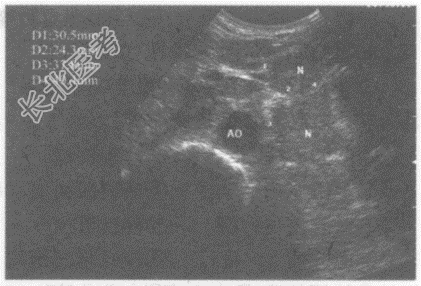

- 单项选择题临床资料:男性患者, 50岁,肺癌术后肝转移。

超声综合描述: 腹主动脉前方可见多个大小不等低回声,最大4.0cm×2.3cm, 边界尚清晰,形态不规则, 部分相互融合。

超声提示: A、腹腔多发肿大淋巴结(淋巴结转移癌)